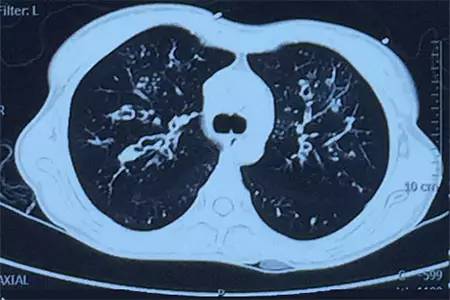

肺CT見(jiàn)下圖

該患者肺部影像學(xué)表現(xiàn)為明顯的支氣管擴(kuò)張,同時(shí)伴有彌漫的滲出斑片影,考慮合并感染,細(xì)菌學(xué)培養(yǎng)提示為綠膿桿菌,結(jié)合藥敏結(jié)果給予頭孢他啶+阿米卡星抗感染,患者存在II型呼吸衰竭予氣管插管機(jī)械通氣支持,加強(qiáng)體位引流排痰,治療18天,患者情況好轉(zhuǎn)出院。